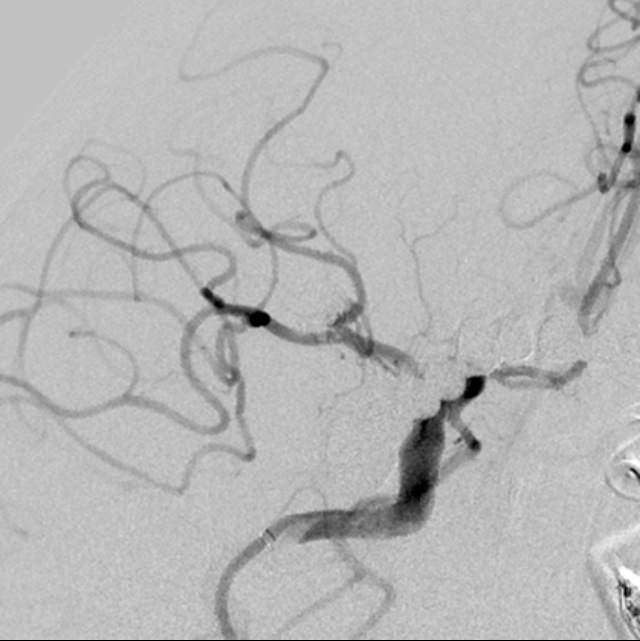

我们在工作中,有时也会遇到比较棘手的问题。譬如下面这个破裂的分叶状的宽颈动脉瘤,两个不大不小不能忽视的子囊还拥有一个共同的大本营—绝对宽颈的瘤体,动脉瘤也通过“犄角之势”成为一个硬骨头,想要拿下它绝非易事。单独出兵(栓塞)容易孤兵深入,首尾难顾,甚至可能需要采用挽救性技术来搬救兵保护粮道(载瘤动脉),万一失利,劳师伤财;使用1-2个支架辅助手术呢,由于急性期抗血小板不足术中可能出现急性血栓堵塞粮道,万一瘤体又不能致密栓塞一网打尽,术后抗血小板吧,怕出血;不抗血小板吧,又担心血栓。一旦遭遇此种境遇,战争(手术)的走向和主动权就无法掌握在指挥者(术者)手中,只能听天由命了……

话归正传,下面我们看看如何分兵使用“犄角之势”的策略夹击栓塞“犄角之势”的硬骨头(分叉部绝对宽颈带有俩角的动脉瘤):两个微导管先后到位,两个子囊内的弹簧圈相互依偎,形成“犄角之势”,共同击杀两者之间的大本营(共同的瘤体),最终致密栓塞动脉瘤,消除了动脉瘤再次兴风作浪(再出血)的风险,也最大限度的保全了各个分支血管(粮道)的安全,急性期也没有使用支架,降低了费用,还保障了安全。